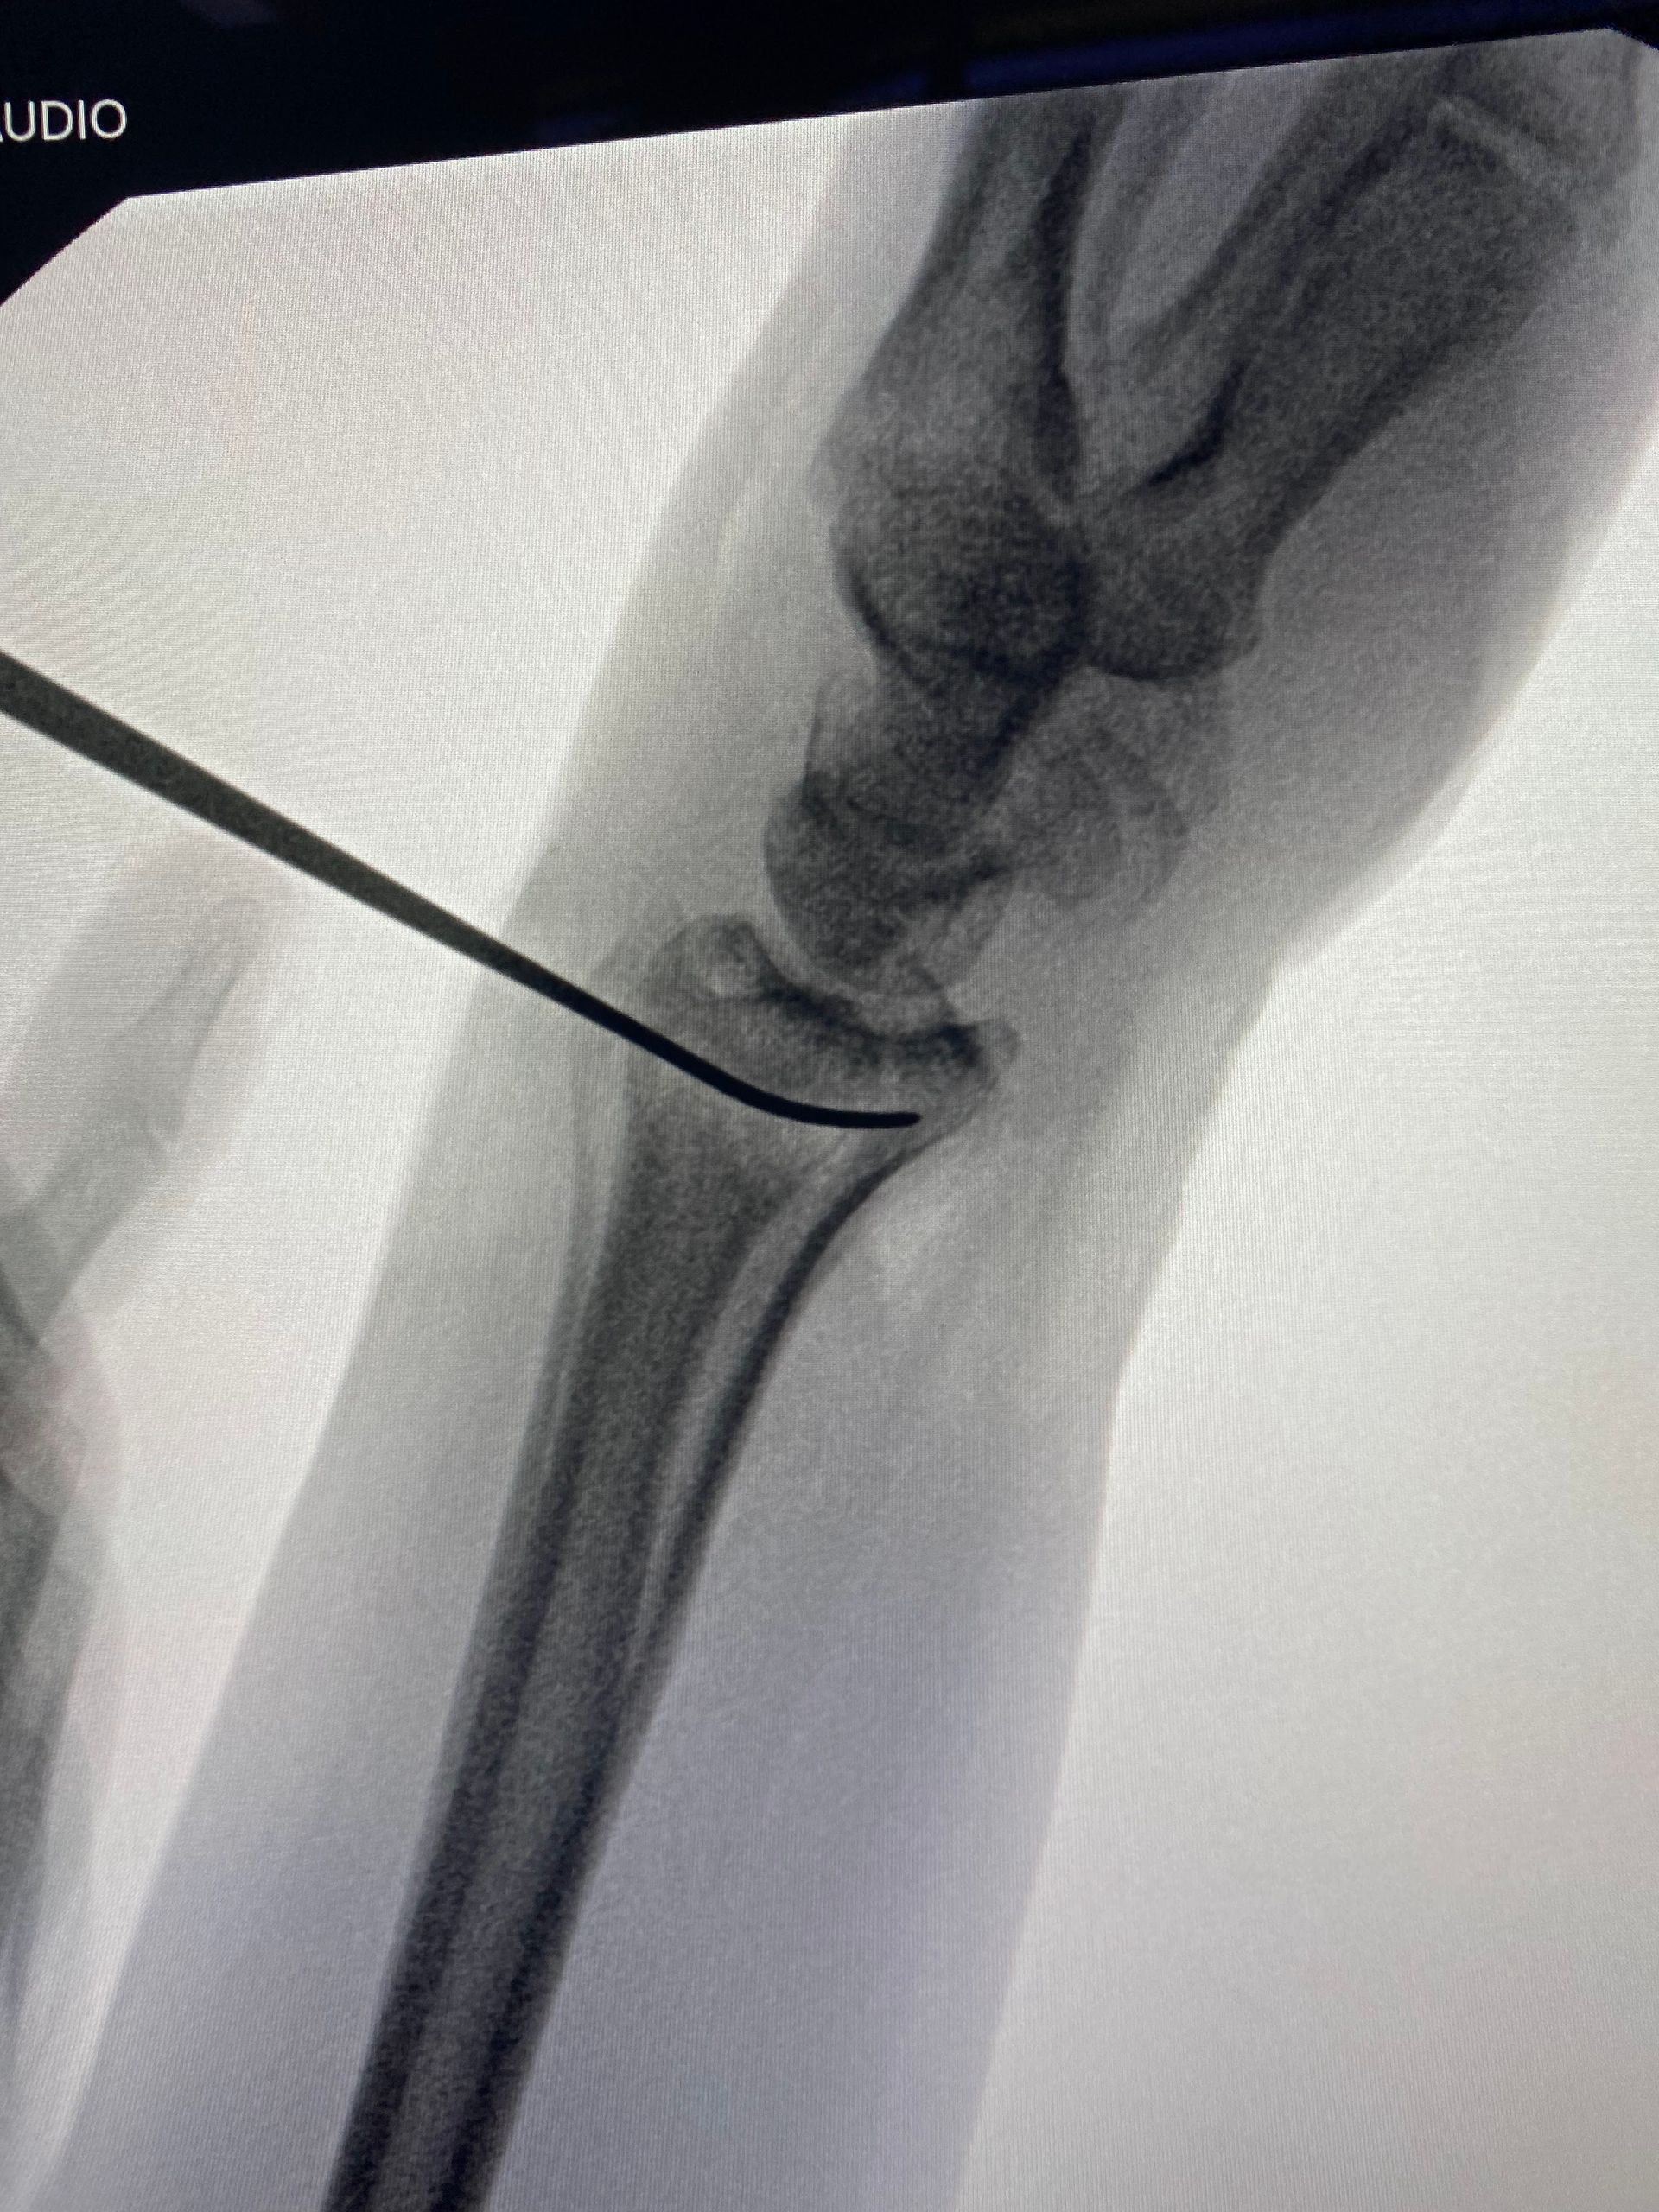

Fernandez tipo III - Fraturas compressivas articulares

- As fraturas tipo "die-punch" são causadas por um trauma axial que causa uma depressão da superfície articular, geralmente na coluna intermediária;

- A redução da fratura de modo preciso está indicada para obtermos resultados ótimos;

- A gravidade da fratura intra articular pode ser difícil de julgar somente pela radiografia, havendo indicação da tomografia computadorizada.

Sequência de imagens na avaliação inicial, radioscopia intra operatória antes da cirurgia, durante a manobra de redução com utilização de um "Freer" e após a fixação da fratura (osteossíntese). A estratégia cirúrgica utilizada envolveu, além da placa e parafusos, o uso de um parafuso canulado introduzido pela borda radial do punho, cuja função foi sustentar o fragmento articular.